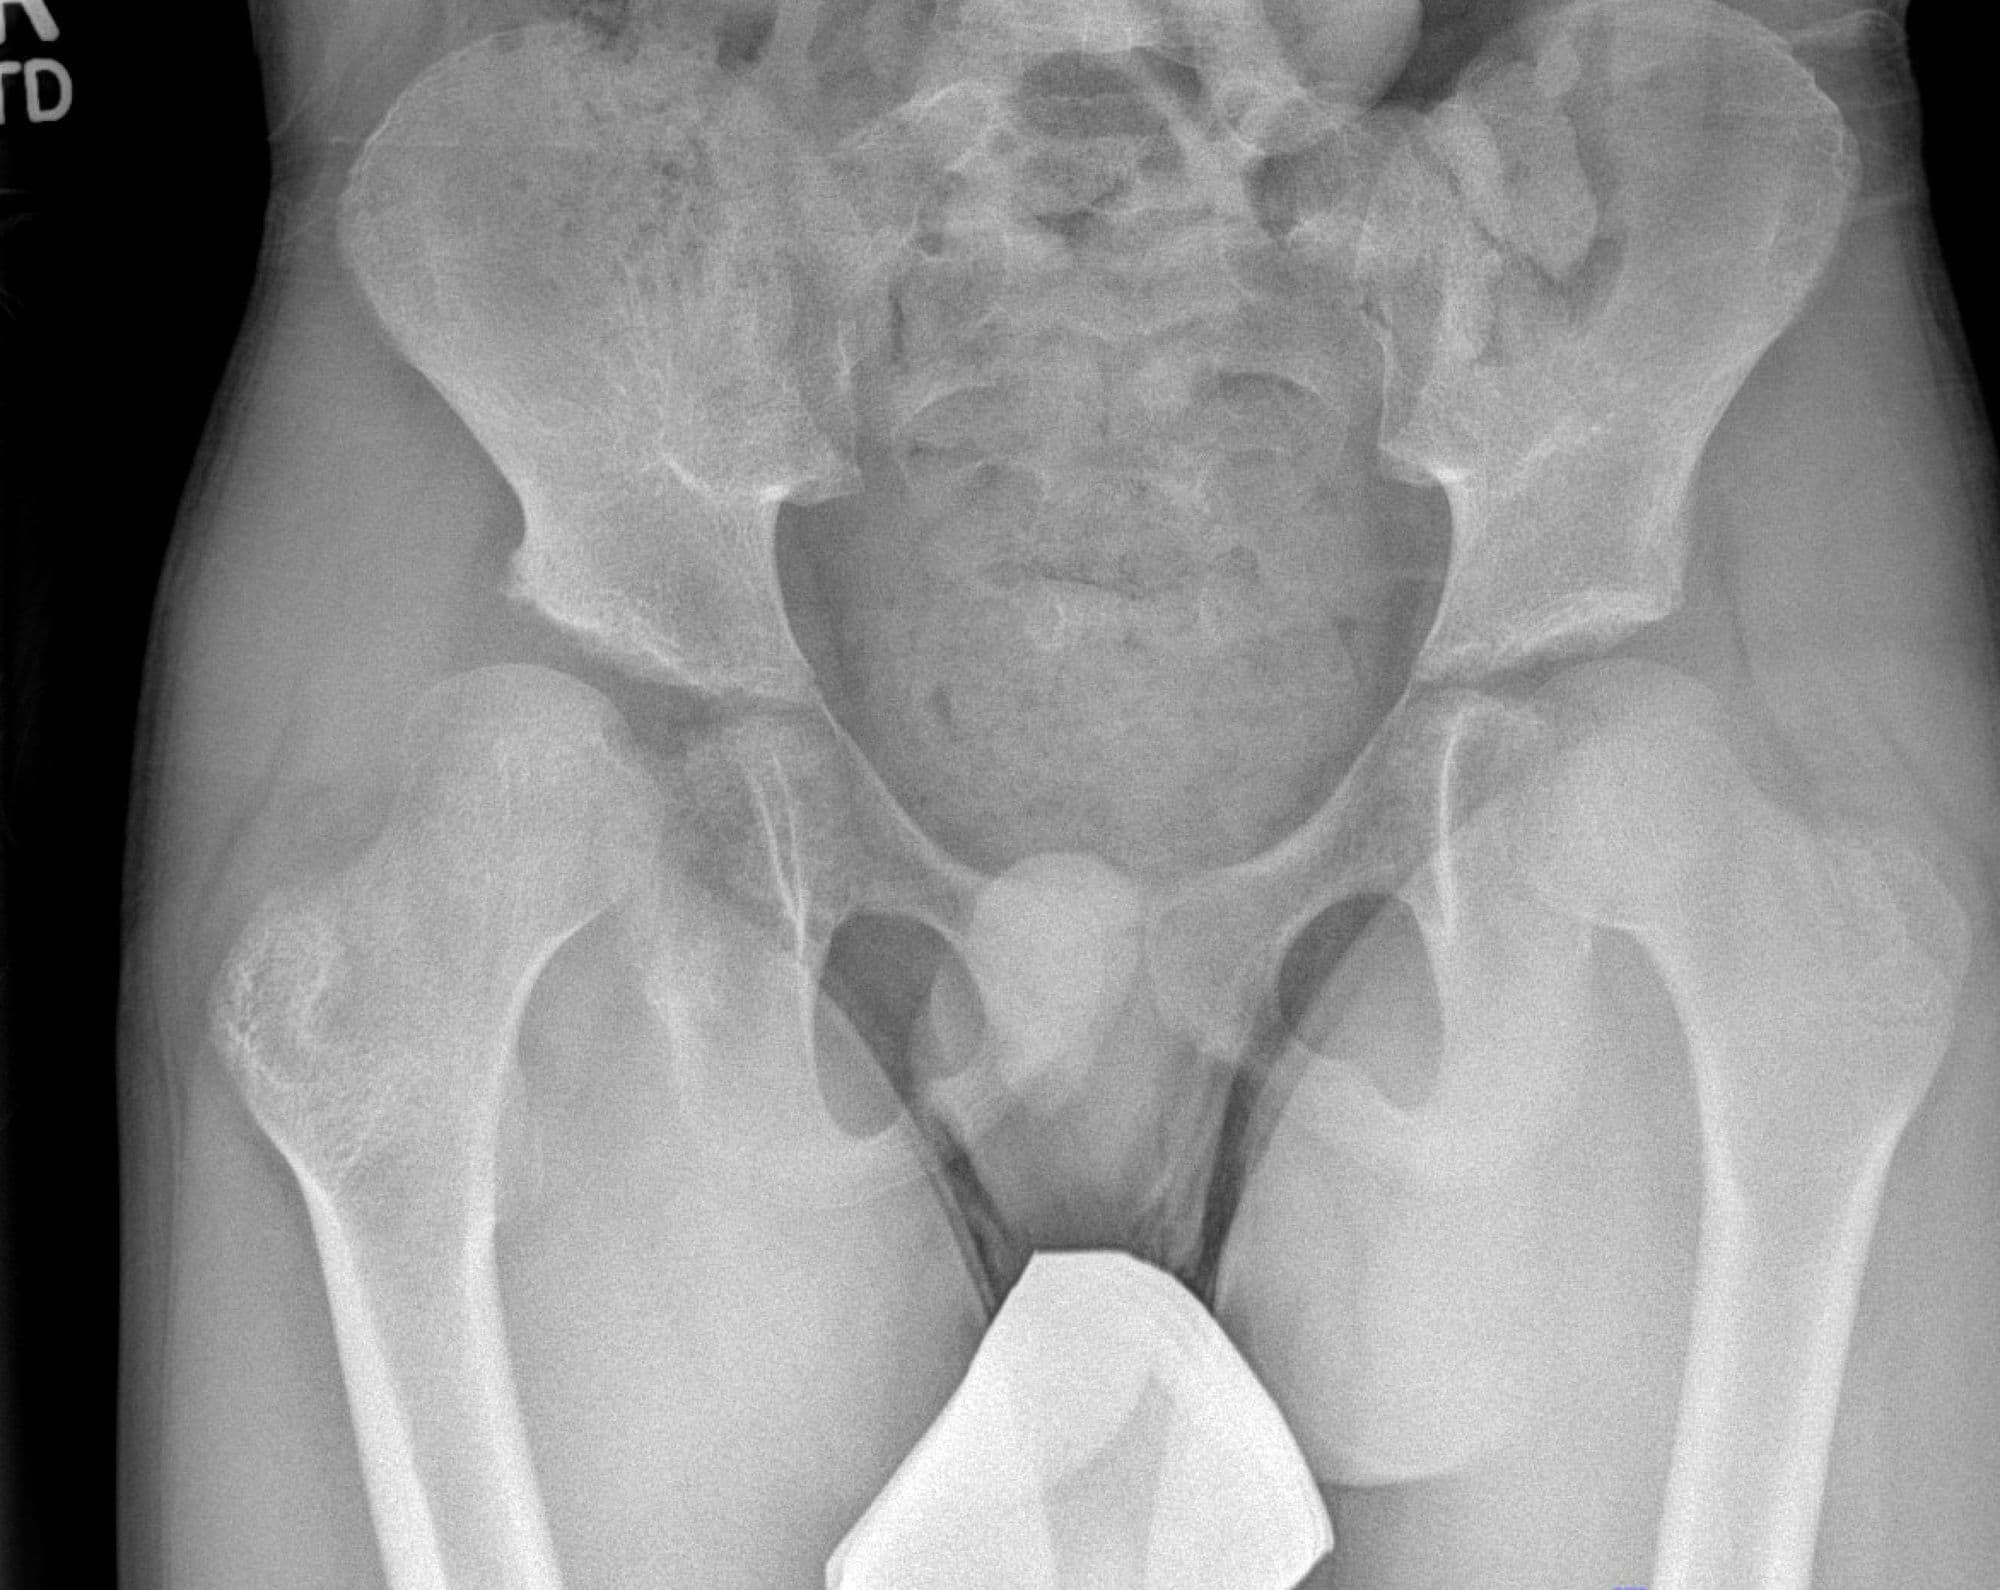

Varus Derotational Osteotomy of Proximal Femur